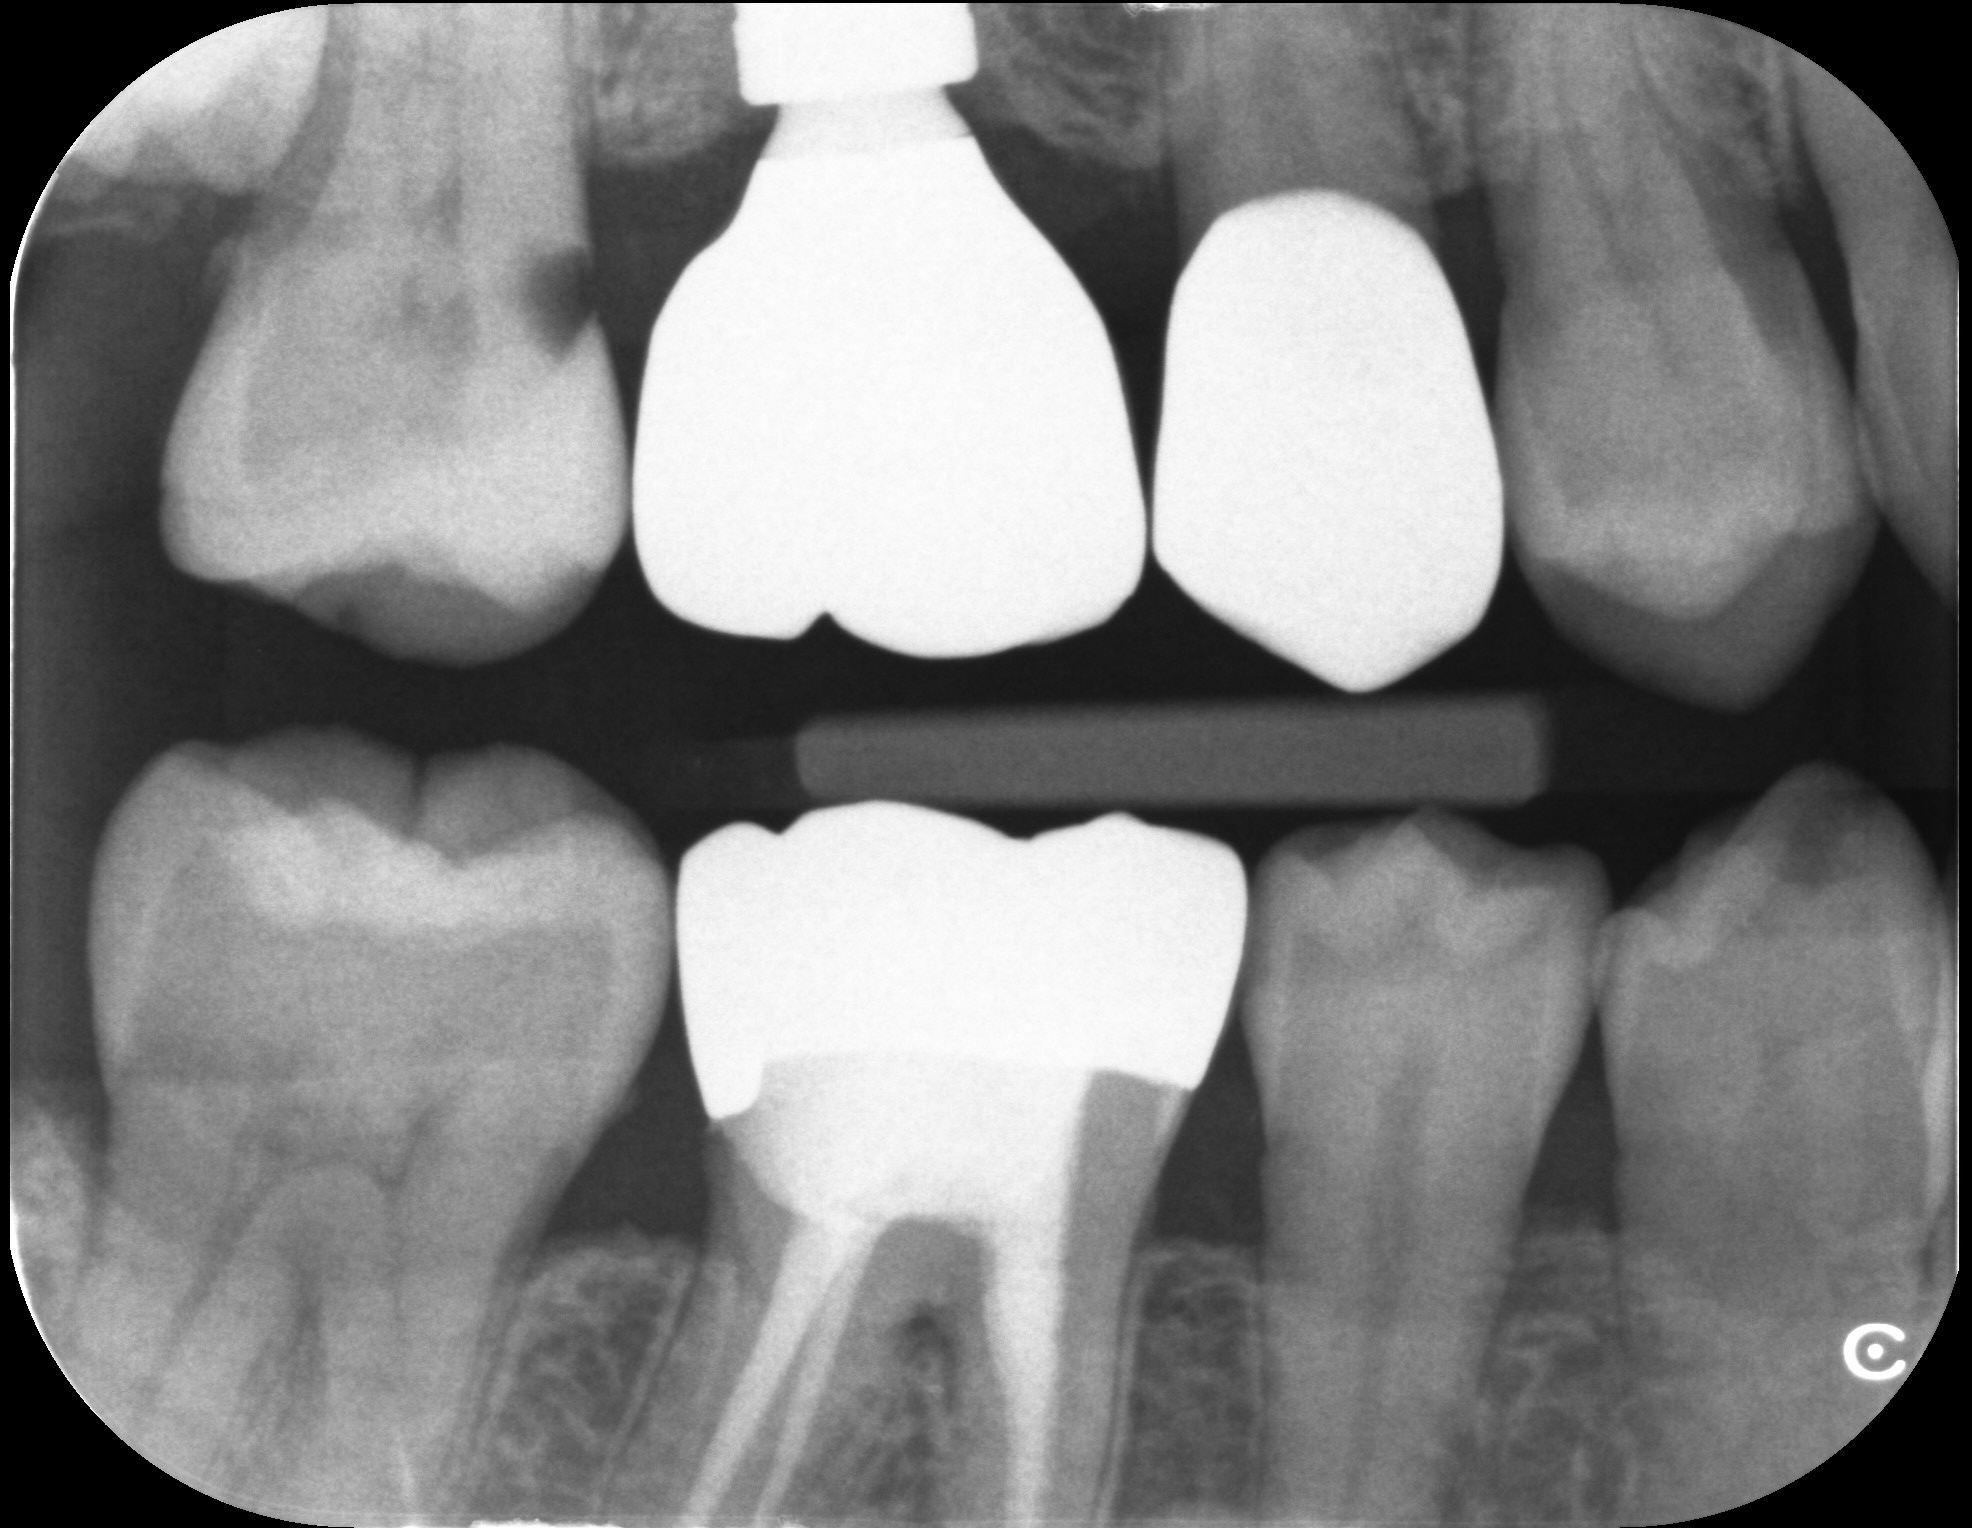

下記の写真は初診時から1年毎に撮影したレントゲンです。

写真の赤丸部分を見ていただくとわかるように、レントゲンで白く見えていた部分が黒くなってきていることがわかります。虫歯が大きくなってくると、このような変化がレントゲンで確認できるようになります。こういった変化を早期に捉え、最小限の治療介入で終わらせることが歯の長期予後につながります。

レントゲンはあくまで撮影した時点での切り抜きに他なりません。小さな虫歯があっても、2年前から同じ大きさなのであれば急いで治療をする必要性はありません。

規格性のあるレントゲン撮影は、必要のない治療を回避し、治療が必要な部分だけを早期介入するための重要な資料となります。

2026